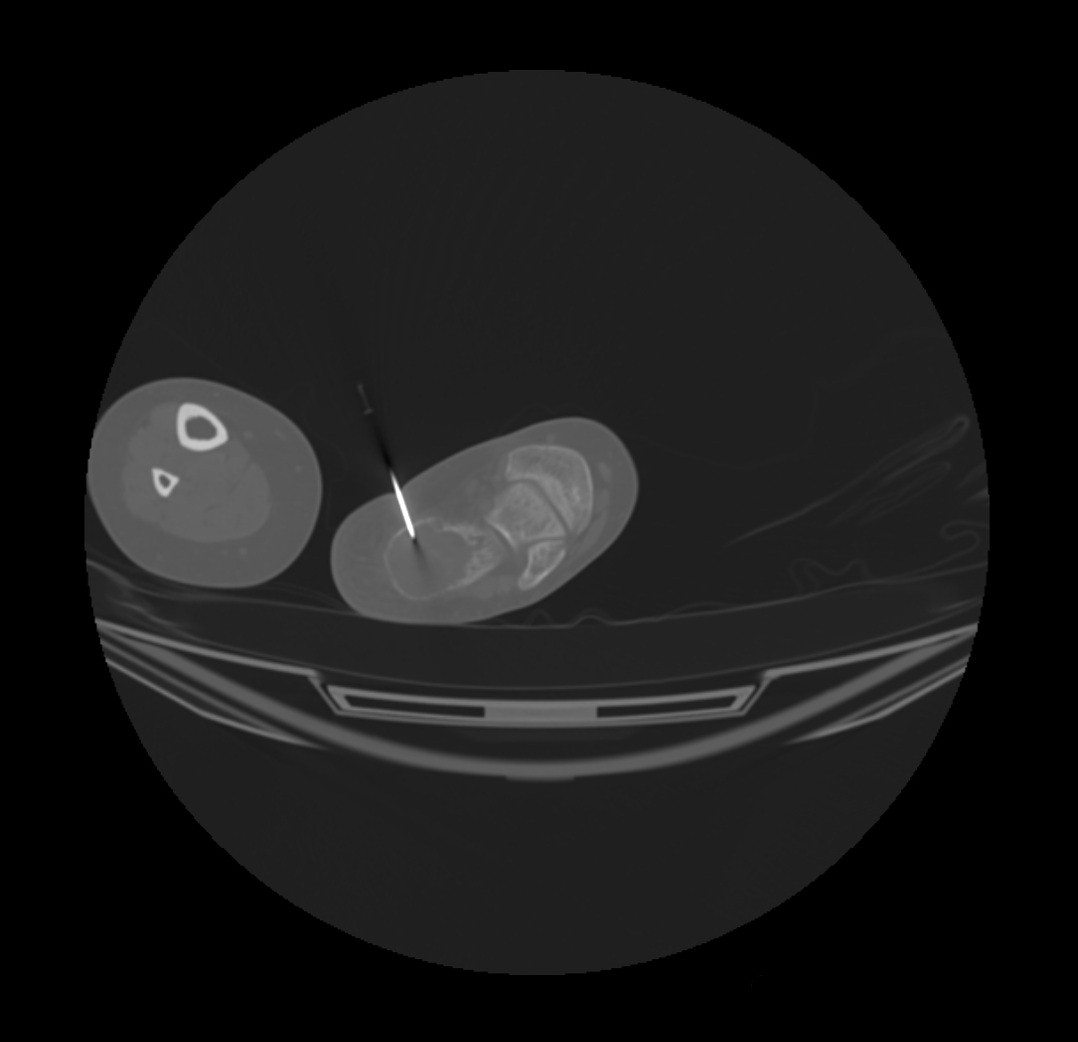

Appearance was consistent with an aneurysmal bone cyst. Orthopedic Surgery was consulted, and a percutaneous CT guided biopsy was performed (Fig. 5).

Figure 5: Intraoperative image showing percutaneous CT guided biopsy of the left calcaneal lesion.